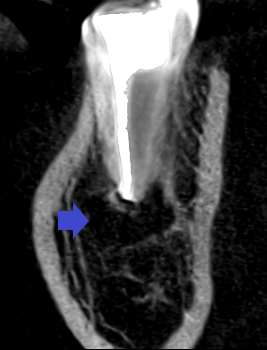

下顎第二大臼歯の初診時の冠状断のCT画像です。

赤い矢印の先に下顎骨を破りそうな位大きくなった膿の影がみられます。青い矢印の先は、下顎管という太い神経の通り道です。下顎管に達するくらいの大きな膿です。ここまで膿が大きいと一般的には、抜歯を勧められると思います。